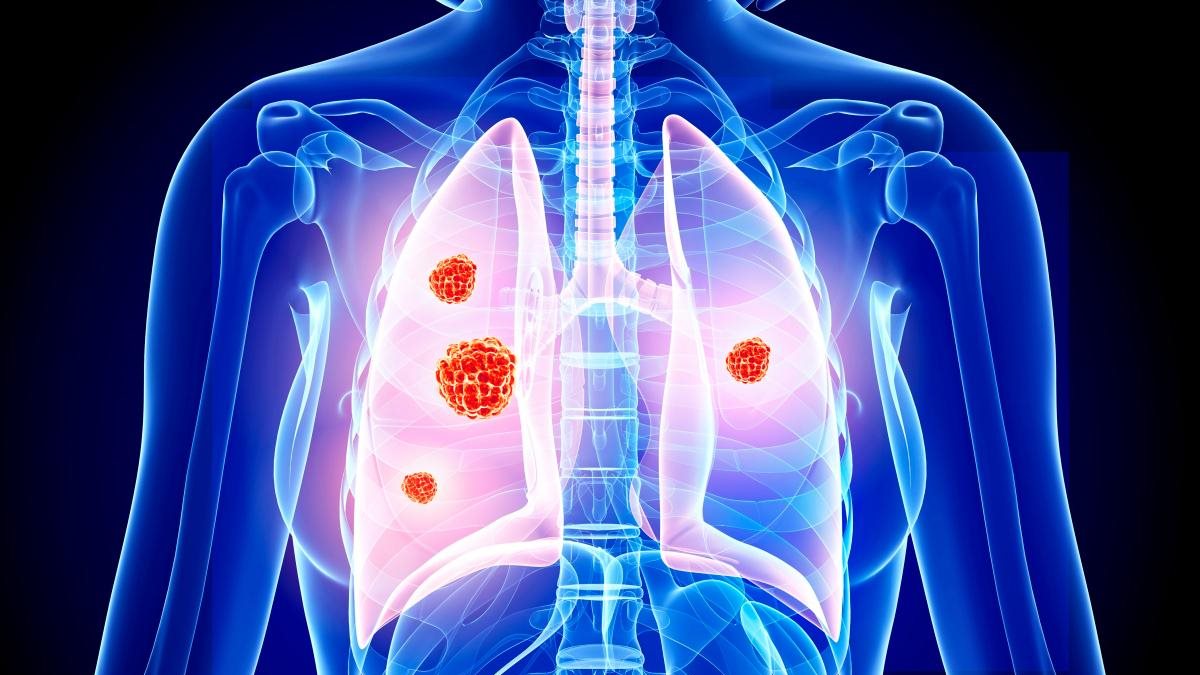

يحدث سرطان الرئة عندما تنقسم خلايا الرئتين بشكل لا يمكن السيطرة عليه، مما يتسبب في نمو الأورام، ويمكن لأي شخص أن يصاب بسرطان الرئة، ولكن تدخين السجائر والتعرض للدخان أو المواد الكيميائية المستنشقة أو السموم الأخرى يمكن أن يزيد من خطر الإصابة.

يعد تدخين التبغ السبب الأكثر شيوعًا لسرطان الرئة، حيث ينجم حوالي 80% من وفيات سرطان الرئة عن التدخين.

ومع ذلك، ليس كل من يعاني من سرطان الرئة يدخن، ويمكن أن يحدث سرطان الرئة بسبب عوامل أخرى، بما في ذلك: